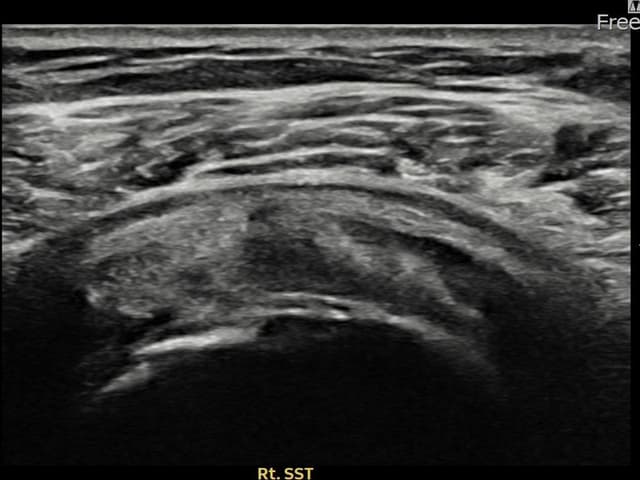

治療実績 — 超音波エビデンス

実際の患者様の施術前後の超音波画像。

手術なしで実現できる回復をご確認ください。

すべての超音波画像は患者様の同意を得て掲載しています。個人差があり、同一の結果を保証するものではありません。

[経過期間: 24.04.26~24.07.05]

[縫縮術] 超音波検査にて右 棘上筋腱 관절면측 광범위 部分断裂(16mm × 5mm (腱厚の約75%欠損))を確認。縫縮術施行後、腱の連続性が回復し、日常生活に復帰されました。